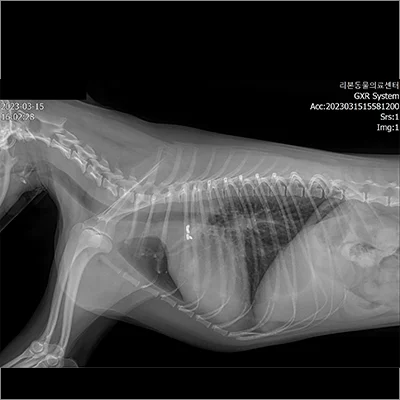

폐엽절제 전

폐엽절제 후